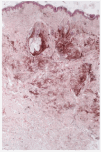

Se practicó una biopsia de la lesión, incluyendo uno de los nódulos profundos, en la que se halló la dermis salpicada por numerosos acúmulos irregulares de melanocitos fusiformes ricos en pigmento y melanófagos, tanto entre los haces colágenos esclerosos de la dermis reticular como en la dermis adventicial perifolicular (figs. 2 y 3).

Fig. 2.--Aspecto histológico a pequeño aumento (hematoxilina-eosina, 20x).

Fig. 3.--Detalle histológico de la lesión que muestra afectación perifolicular (hematoxilina-eosina, 80x).